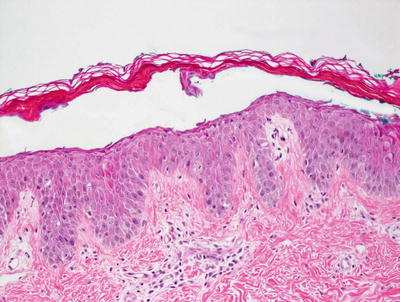

The histologic findings of acropustulosis of infancy are not specific, but characteristic of this entity. The epidermis has foci of spongiosis with microvesiculation [2] (Fig. 3.3). Neutrophilic abscesses are present within the vesicles (Fig. 3.4). Acute lesions do not have parakeratosis, although this is a common finding in more established lesions. Less commonly, eosinophils may be present within the microvesicles [3].

Fig. 3.3

Histologic features of acropustulosis of infancy include intraepidermal spongiosis and clusters of neutrophils within the stratum corneum